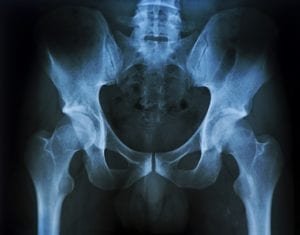

Acute hip injuries often happen in the workplace. Whether through a slip and fall accident, repetitive stress, a motor vehicle accident, or some combination of those factors, work-related hip injuries are painful and difficult to treat. This is especially true where an injury is so severe that the injury victim needs a hip replacement and the associated medical care.

This article will examine different types of work-related hip injuries and their respective medical treatments. We’ll also look at some examples of what a workers’ comp claim for a hip injury might look like. Most importantly, we’ll estimate the amounts of workers’ comp hip injury settlements in different situations.

We’ll look at some of the more common types of work-related hip injuries, along with examples of potential workers’ compensation settlements for each type of injury claim.